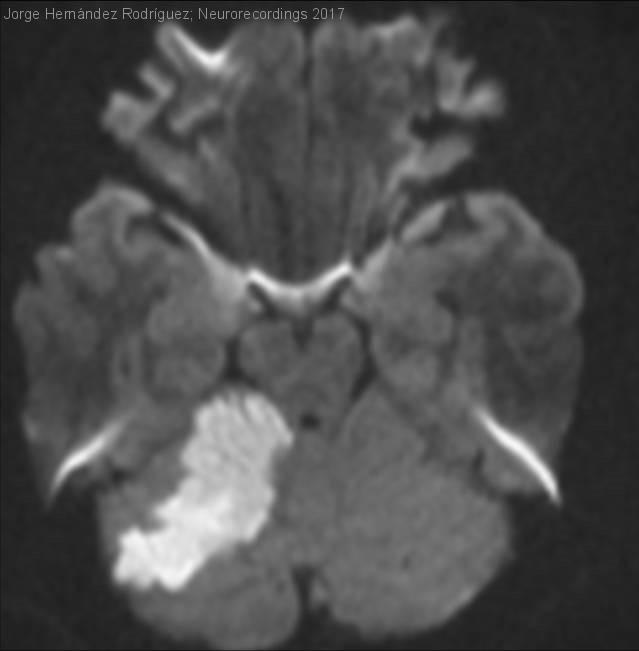

Diagnóstico final: Ictus cerebeloso derecho en paciente jóven. Foramen oval permeable.

Varón de 28 años de edad, diestro, trasladado desde el Servicio de Neurocirugía con el diagnóstico de infarto cerebeloso derecho.

A.P: Fumador de 20 cigarillos/ día. Intervenido de sinus pilonidal el día 10/08/17.